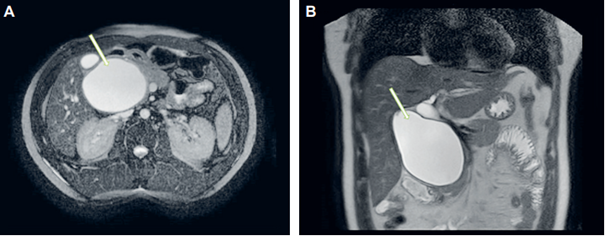

Paciente masculino de 35 años, sin antecedentes médicos, con cuadro clínico de 5 meses de evolución consistente en dolor abdominal, de predominio en hipocondrio derecho, que se irradiaba a espalda. Los paraclínicos mostraron leve leucocitosis, proteína C reactiva elevada, perfil hepático con hiperbilirrubinemia a expensas de la bilirrubina directa, fosfatasa y amilasa elevadas. En la colangiorresonancia se evidenció la presencia de un quiste del colédoco de tipo IC (Figura 2).

Posterior a la valoración por Cirugía hepatobiliar se consideró realizar un abordaje quirúrgico con resección del quiste del colédoco y la vesícula biliar, más reconstrucción de la vía biliar mediante derivación biliodigestiva por vía abierta. En el transoperatorio se halló un quiste del colédoco con compromiso desde el conducto hepático común hasta la zona intrapancreática, de aproximadamente 14 cm de diámetro, que adicionalmente comprometía la vena porta y la arteria hepática derecha (Figura 3). El procedimiento fue realizado sin complicaciones y el posoperatorio se desarrolló de manera adecuada, sin fístula postoperatoria, por lo cual se retiró el dren al tercer día postquirúrgico y se dio egreso al día siguiente.